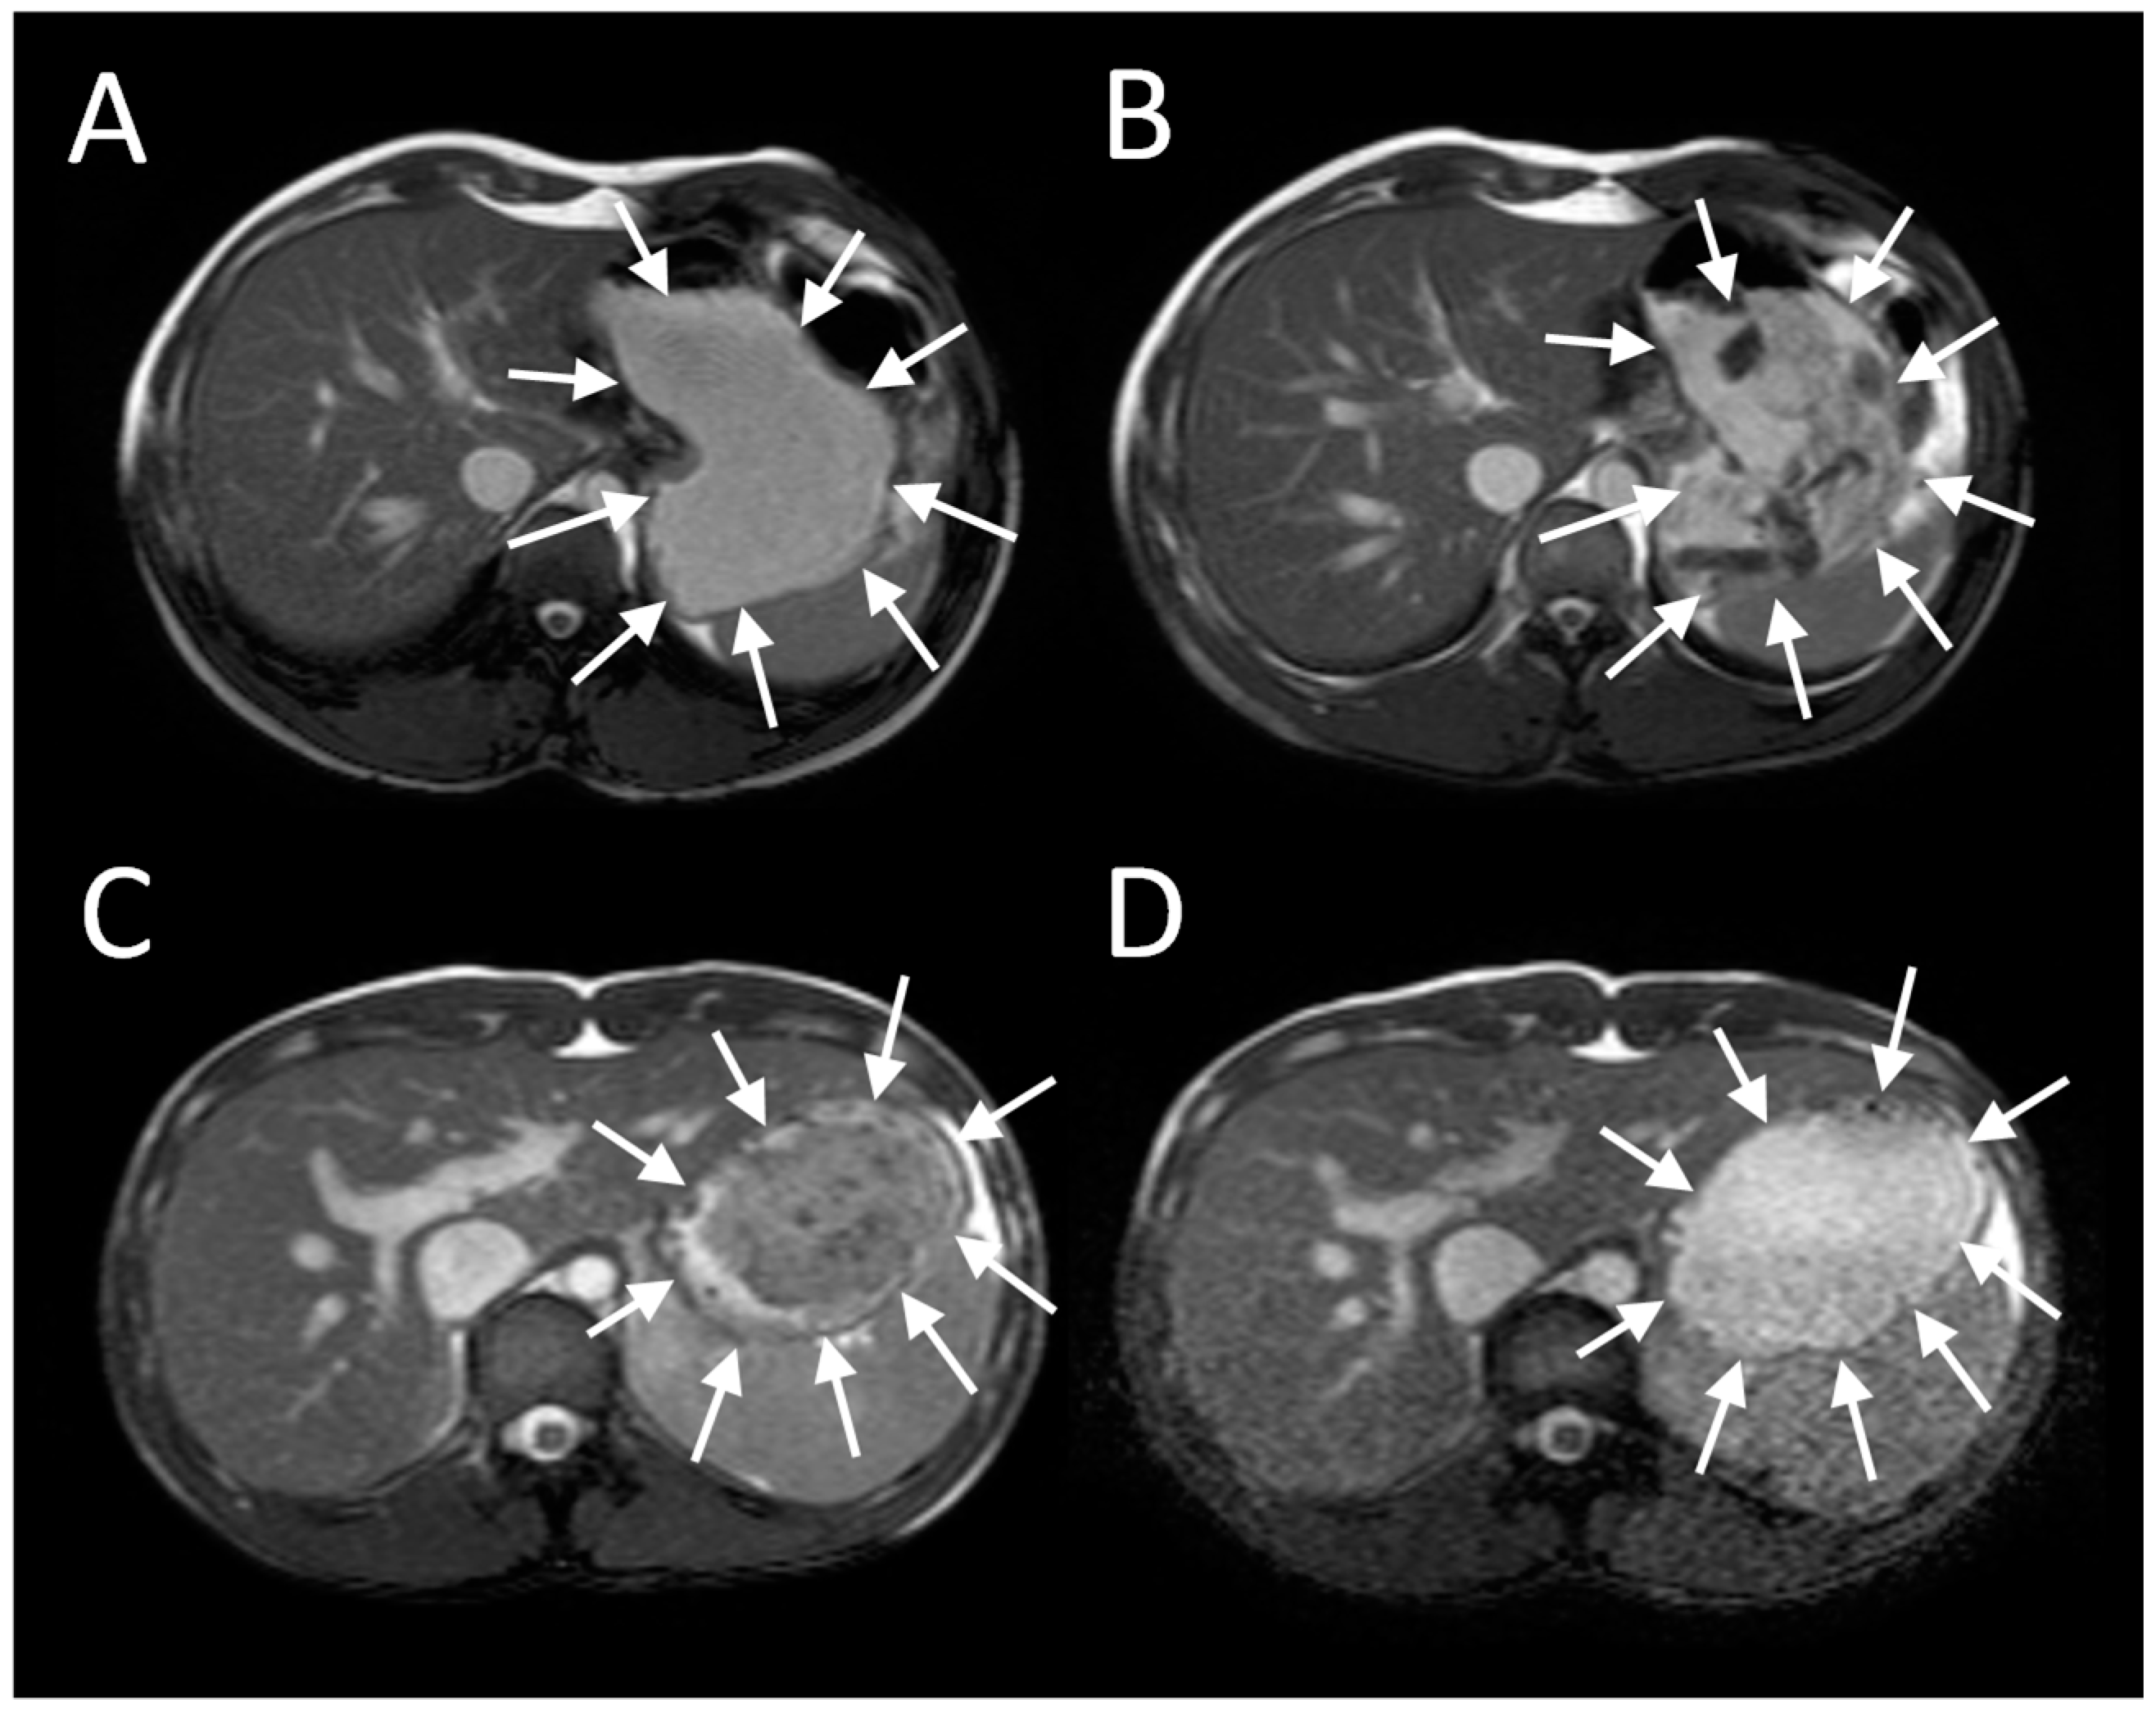

Imaging of intra-gastric contents demonstrates a wealth of detail previously unrecognized and unmeasurable when studies were limited to measurement of merely the rate of gastric emptying using scintigraphy (Figure 1). When food is ingested, chewing and mixing with saliva play a crucial role in modifying its consistency to form a bolus, whose physical properties allows easy passage past the larynx and down the oesophagus into the stomach [1]. The successive food boluses are accommodated within the stomach by reflex fundal relaxation. Soon after ingestion, antral contractions, starting mid-way down the lesser curvature, elute material from the outside of the solid component of the meal into the antrum and thence through the pylorus. MRI sequences sensitive to flow have been used to demonstrate the backward and forward movements induced by a combination of antral contractions and pyloric closure, which results in both retropulsion of contents back into the antrum and propulsion of a fine stream through the pylorus [2]. The retropulsive movements we observed were most marked after mixed nutrient fat/protein/carbohydrate meals compared to 5% or 10% glucose. The shear forces generated by antral grinding are surprisingly small compared to those in the mouth, and when assessed from the force required to break agar gel beads were found to be <0.65 newton [3].

The antral contractions are typically propulsive as they commence in the mid stomach but as they approach the pylorus change to a more systolic pattern with pyloric closure occurring before all the chyme is expelled into the duodenum. This effectively restricts gastric emptying to particles <2 mm in diameter and creates shearing forces as the remaining material is forced backwards away from the contracting pylorus. The resulting forward and backward flows can be detected using flow sensitive MRI sequences as mentioned previously. The net effect is the earlier emptying of the fluid component of mixed liquid/solid meals, which make up most of what normal humans ingest. MRI images can clearly show the heterogeneity of food immediately after food ingestion, which varies according to the meal type (Figure 1). A rice pudding meal typically separates into an uppermost fluid layer above a dependent solid component, whereas a roast chicken and vegetable meal produces a very heterogeneous intragastric distribution of solid and liquid. Other more homogenous meals like porridge, soup or bread produce a uniform intra-gastric mass from which no separation of the liquid and solid phase is possible. When we compared an equicaloric rice meal with wholemeal bread, we found that while the rice pudding meal separated into a solid and liquid phase, the wholemeal bread formed a rather homogeneous mass with no clear separation of fluid and solid. While the rice meal allowed the stomach to sieve the meal and empty the fluid faster than the solid, sieving was not possible with the more homogeneous bread meal and as a consequence the gastric volume fell more slowly. In contrast, once the wheat entered the small intestine it was rapidly absorbed and the small bowel water content (SBWC) was consistently lower than after the rice meal postprandially, suggesting than any sensation of bloating after a bread meal most probably comes from gastric distension [4]. Other groups have also used MRI to document gastric sieving and its prevention by homogenization with both solid [6] and liquid [7] meals.

Figure 1. Gastric MRI images of different mixed solid/liquid meals: (A) Soup, (B) roasted chicken and vegetables, (C) whole wheat bread and (D) rice pudding. Reproduced from [4], Springer Nature 2013, under Creative Commons CC-BY license and from [5], Oxford University Press 2012, with permission.